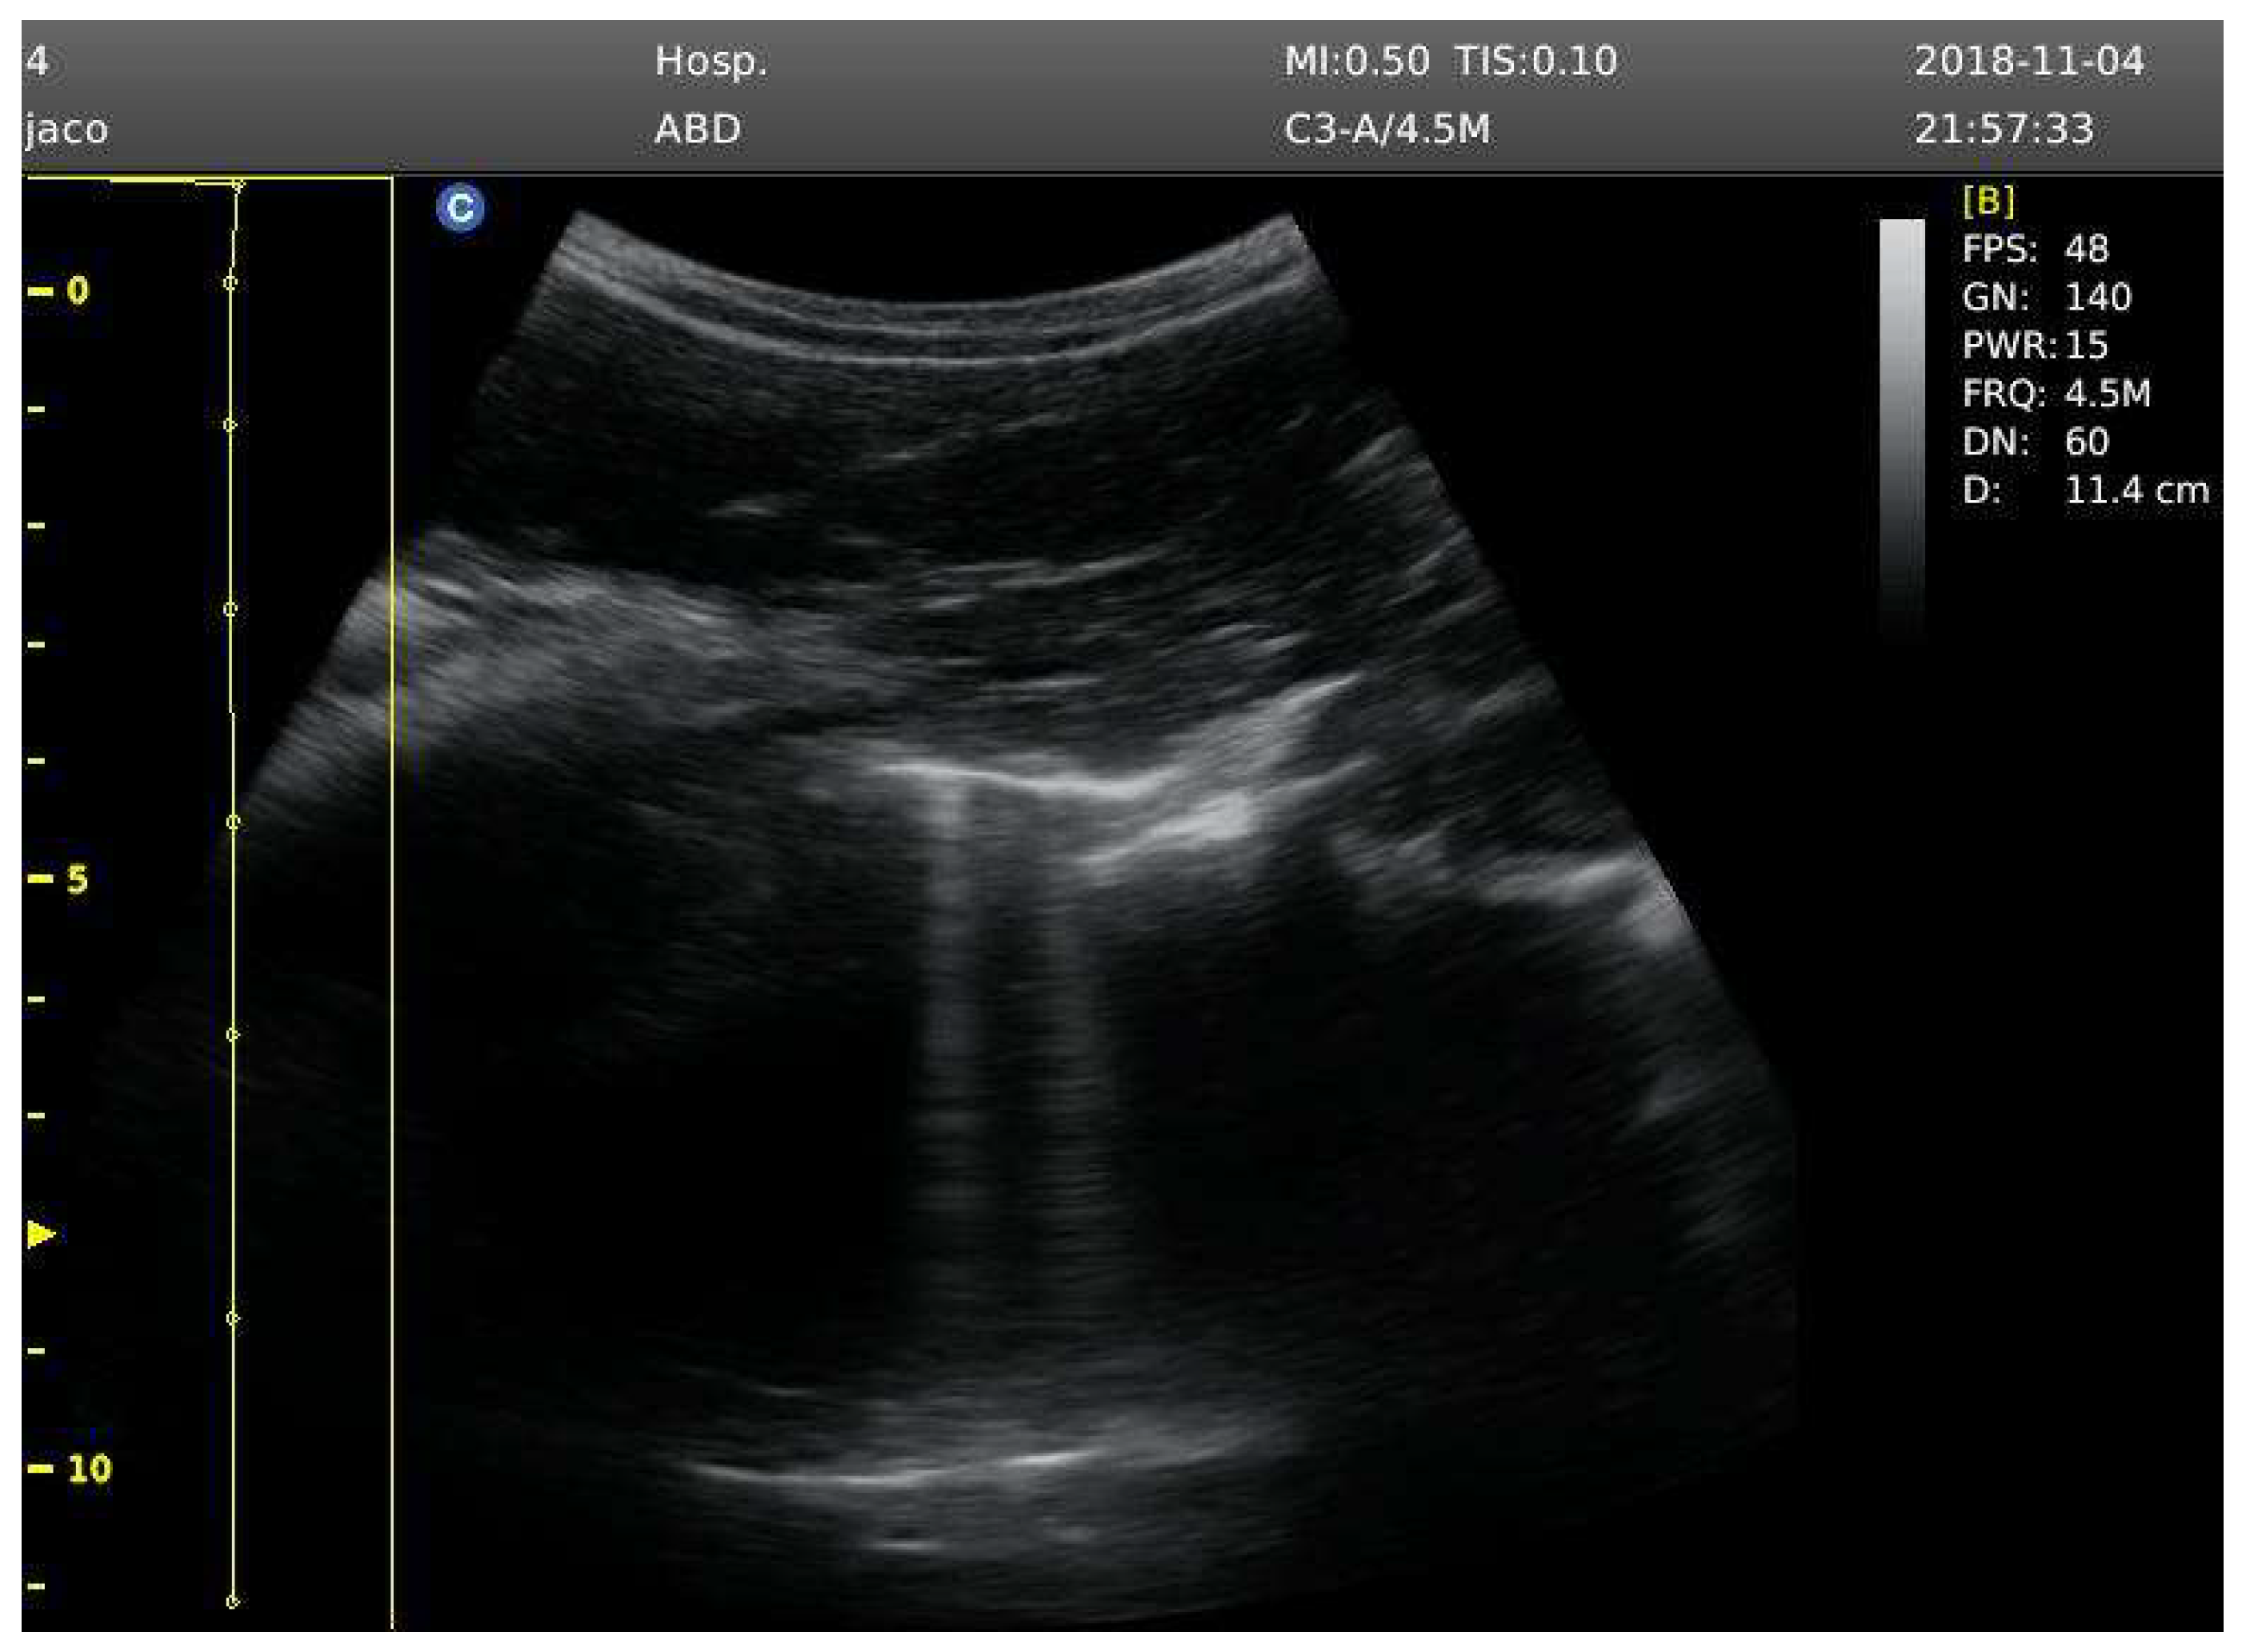

Baseline ultrasound B-lines were recorded before the competition, with participants not having conducted diving activity 24 hours before the assessment. Lung ultrasound was collected in the sitted position by displaying mode B, using 2D ultrasonic imaging, with a convex transducer 3.5 MHz (Chison ECO 5 Portable Ultrasound Scanner). Bilateral imaging of the hemithorax from the second to fourth intercostal spaces was performed, culminating in 6 assessment zones.

A B-line was detected as an echogenic comet-shaped signal spreading from the pleural line to the further border of the screen. The same medical researcher (E-P) performed all ultrasound measurements; then, B-lines were analysed by another medical researcher specialist on pulmary ultrasound (J-L) to provide a total B-line score [13].Ultrasound B-lines are an index of extravascular lung fluid, and the sensitivity a reliability of this method has been contrasted in different studies compared with radiographic imaging [14], [15]. After analysis, the total number of B-lines was recorded to detect possible signs of pulmonary edema.

Four participants showed signs of mild pulmonary edema, after diving, coinciding in both protocols (Supp material 1). Ultrasound B-lines count was recorded at baseline, 10 minutes post-immersion and at 1 hour post-immersion (Figure 1).

Figure 1. Signs of ultrasound B-lines.